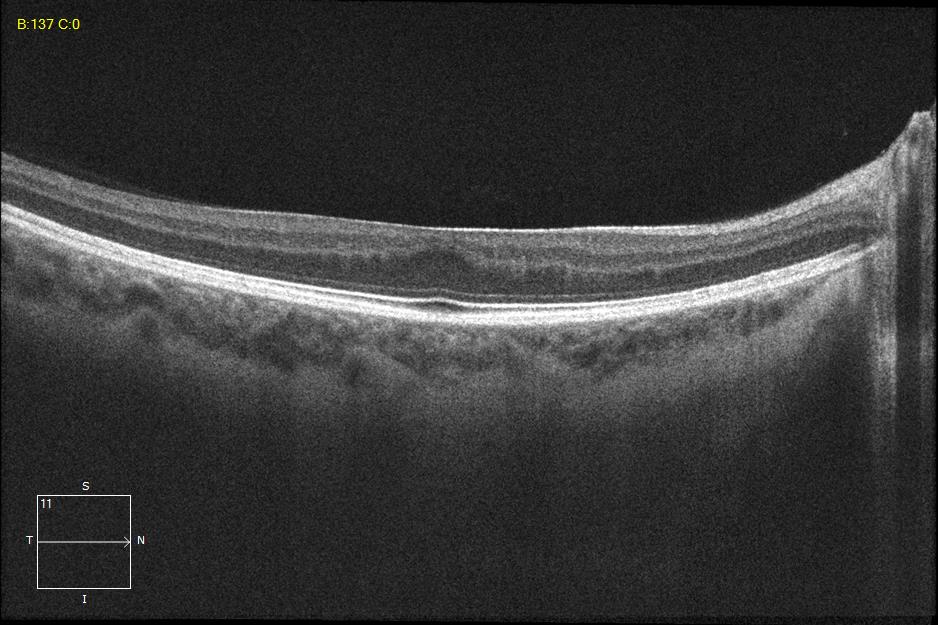

Two different patients with isolated foveal hypoplasia grade 2. The definitions of fovea plana and foveal hypoplasia have led to controversy among experts. The term fovea plane refers to the anatomical absence of a foveal pit. An estimated 3% of children with clinically normal eyes have an underdeveloped foveal pit on OCT. According to some experts, a foveal pit is not absolutely necessary for foveal cone specialization. A diagnosis of fovea plana alone does not automatically herald functional disability. It is possible to maintain adequate visual acuity in an eye with a fovea plana. Foveal hypoplasia refers to an underdeveloped fovea with vision loss. Foveal hypoplasia has also been seen in conditions such as aniridia, albinism, achromatopsia, nanophthalmus, and incontinence. pigment and premature retinopathy.

In contrast to other definitions, Thomas et al. defined foveal hypoplasia as the persistence of inner retinal layers in the fovea and developed a grading system based on optical coherence tomography features. According to this grading system, grades 2, 3, and 4 of foveal hypoplasia corresponded to the fovea plana.

Grade 2 foveal hypoplasia has all the features of grade 1, except that there is no pit.